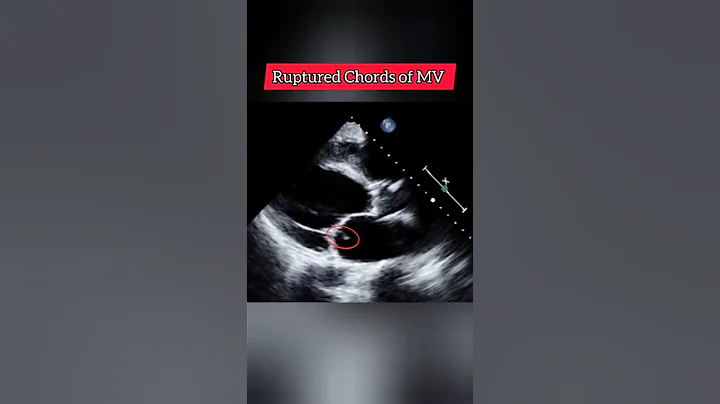

How to measure IVRT on Echocardiography?